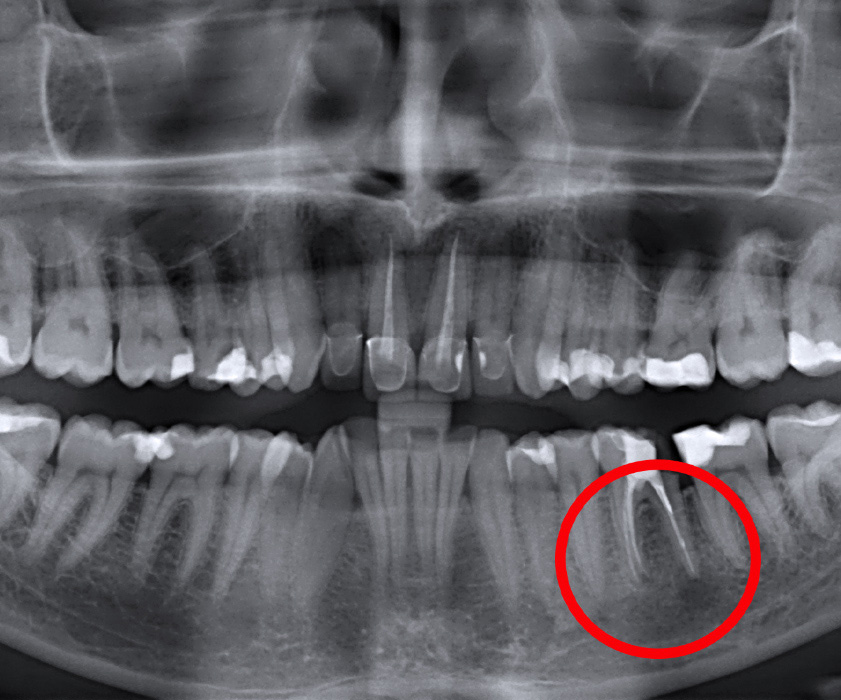

Die Apikotomie ist ein chirurgischer Eingiff der Mundchirurgie, wo die Spitze der Zahnwurzel (Apex), meist durch die chronischen Entzündungen oder den Bruch an der Spitze der Wurzel (Granulom oder Zyste) entfernt wird.Die Apikotomie wird unter Lokalanästhesie durchgeführt, was bedeutet, dass die Behandlung schmerzfrei ist. Im Zentrum für Zahnheilkunde Dr. Štimac führt der Apikotimie Eingriff Dr. med. dent. filip Štimac, Spezialist in der Mundchirurgie, durch.

Alveolotomie ist die chirurgische Entfernung des impaktierten und retinierten Weisheitszähne. Für einzelne Zähne kann das Wachsen verhindert werden, aber das bedeutet nicht dass die Entwicklung der Zähne angehalten ist. Die impaktierten und retinierten Zähne sind Zähne, die vollständig innerhalb des Knochens formiert wurden, aber sie haben nicht in ihrem Ort oder in jedem anderen Ort im oder aus dem Zahnbogen entstanden.

Zystektomie ist die Entfernung periapikaler Läsionen der Zähne bzw. Abszesse, Granulome und verschiedener Zysten.